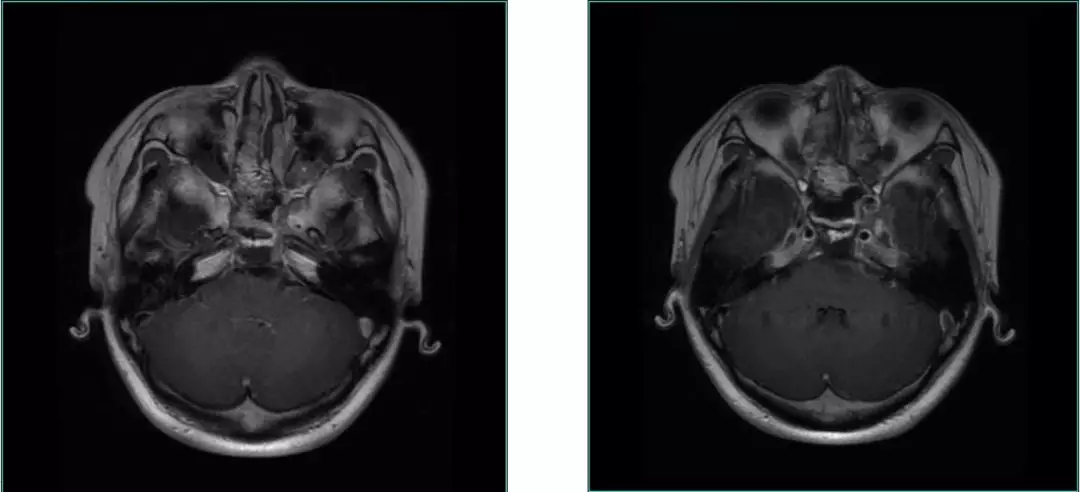

Post-op MRI with contrast

Post-op MRI

Pathological Result

Chordoma

Immunohistological Results:CK(+),VIM (+) ,PR (-),S-100 (+),GFAP,EMA (+),Ki67 (15%+),Desmin(-),Calponin(-),ER(-)。

General condition is good.

No CSF fistula, double Vision improved.